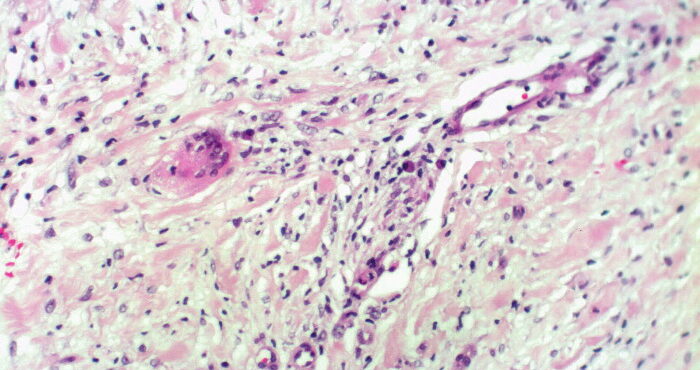

Necrobiois lipoidica diabeticorum = النخر الشحماني السكري Necrobiosis Lipoidica Necrobiosis lipoidica is an idiopathic disorder typified by indurated plaques of the shins . In 1966, in a large series, Muller and Winkelman reported that two thirds of patients with necrobiosis lipoidica had overt diabetes at the time of diagnosis {82}. Of the rest, all but […]